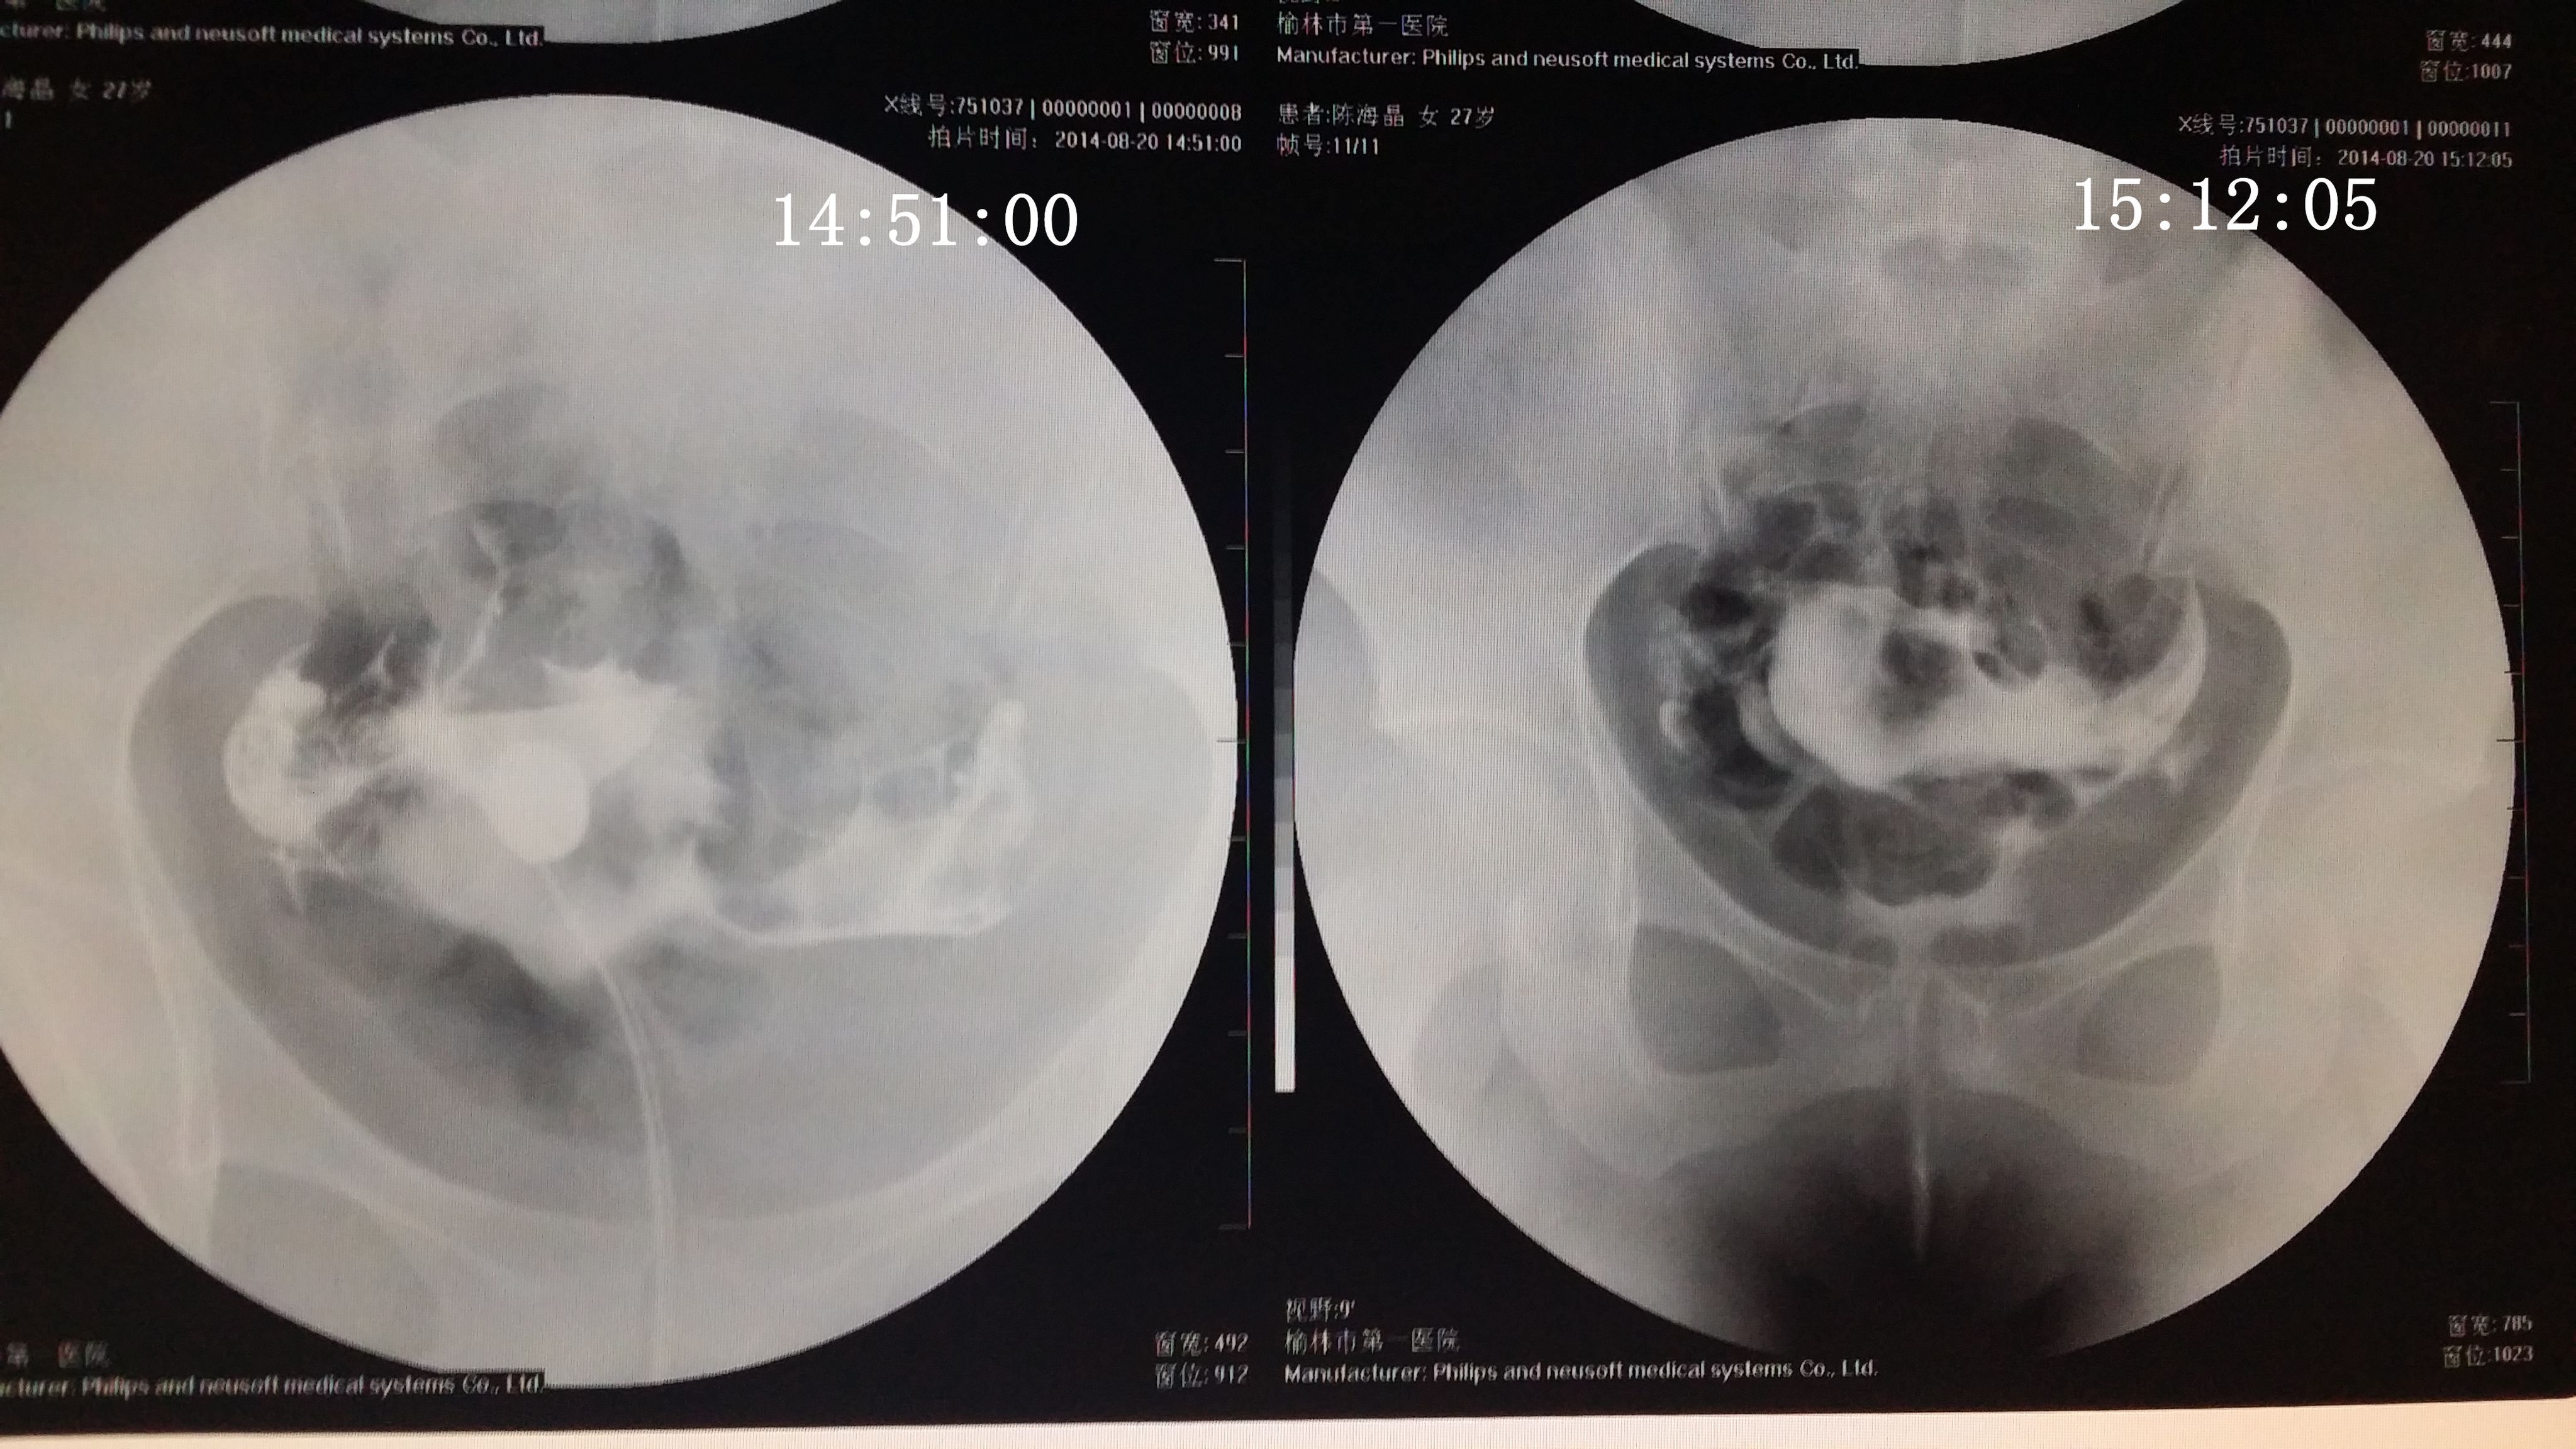

请专家帮我分析下我的造影片 医生诊断说是没问题,只是右侧输卵管伞部有点弯曲不直,说左侧通着可以自 然受孕,不知道会不会有错,之前在其他医院没做造影直接做的通液,说是阻力很大,堵的厉害,后过几个月在另一家医院做的这个造影片。(另之前有过盆腔积液,但已经治疗好了} 造影都好几天了右侧一直觉得酸痛的,是不是又发炎了啊,吃药可以吗? 点击展开 匿名用户 2014-09-04 20:08 为您推荐: 其他回答 你好,现在这个时候你不要太担心的竟然是已经检查过了之后的话那就不要剪的啦,因为这个时候已经通开了, 可靠的悠闲80 2014-09-05 12:50 相关问题 输卵管通而不畅,迂曲右侧上举,请问济南哪个大医院治疗这个专业啊~请有经验的人告诉下~急急急另附造影片 输卵管伞端不通怎么办 如果排了,B超能检测出来吗?B超单上会显示什么?12月22号做的造影,结果是右侧输卵管伞端通而不

然受孕,不知道会不会有错,之前在其他医院没做造影直接做的通液,说是阻力很大,堵的厉害,后过几个月在另一家医院做的这个造影片。(另之前有过盆腔积液,但已经治疗好了} 造影都好几天了右侧一直觉得酸痛的,是不是又发炎了啊,吃药可以吗?